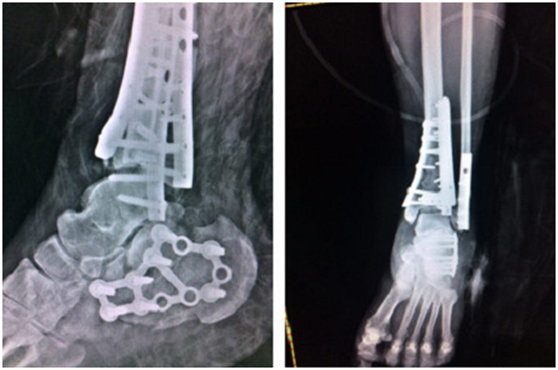

(術后)

4月上旬,俞光榮教授和足踝科徐明亮手術小組共同為華大姐進行了“左pilon骨折及左跟骨骨折切開復位內(nèi)固定術”,手術進行了4個小時,非常成功。

“患者是雙pilon骨折,雙跟骨骨折,腰椎部位還多發(fā)骨折,手術不能一次做完,得分期做。一次做完的話手術時間太長容易感染,病人也承受不了。”徐明亮主任說。